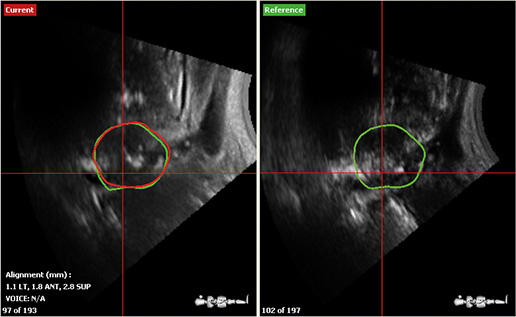

Eskalacja dawki w radioterapii wydłuża czas życia wolnego od nowotworu 1. Aby chronić organy krytyczne stosuje się zmniejszone marginesy dla obszarów tarczowych, co wymaga jeszcze dokładniejszej ich lokalizacji. łożenie pacjenta z wykorzystaniem obrazów portalowych wiąże się ze znaczącymi ograniczeniami głównie ze względu na uzależnienie od struktur kostnych jako typowych punktów odniesienia. W przypadku prostaty stosuje się wszczepianie złotych…